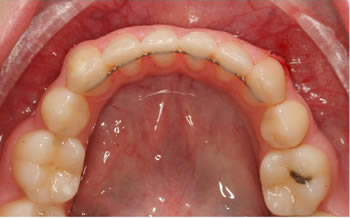

Fixed Retainers

Lingual wire

Where possible, we place a fixed retainer on the lower teeth. This is called a lingual bond.

This requires a wire to be bonded on the inside of the lower front teeth.